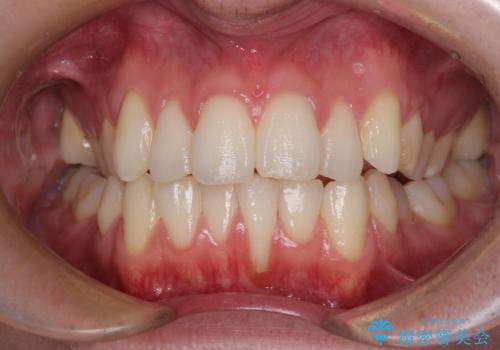

ほぼ歯根全てが露出 2度の歯肉移植術で自然な見た目に

1回目の処置で多少は被覆され歯肉が厚くなりましたが、十分とは言えなかったため、2回目の処置を行いました。

2回目の処置後には十分な厚みと、十分な被覆量を獲得することができました。